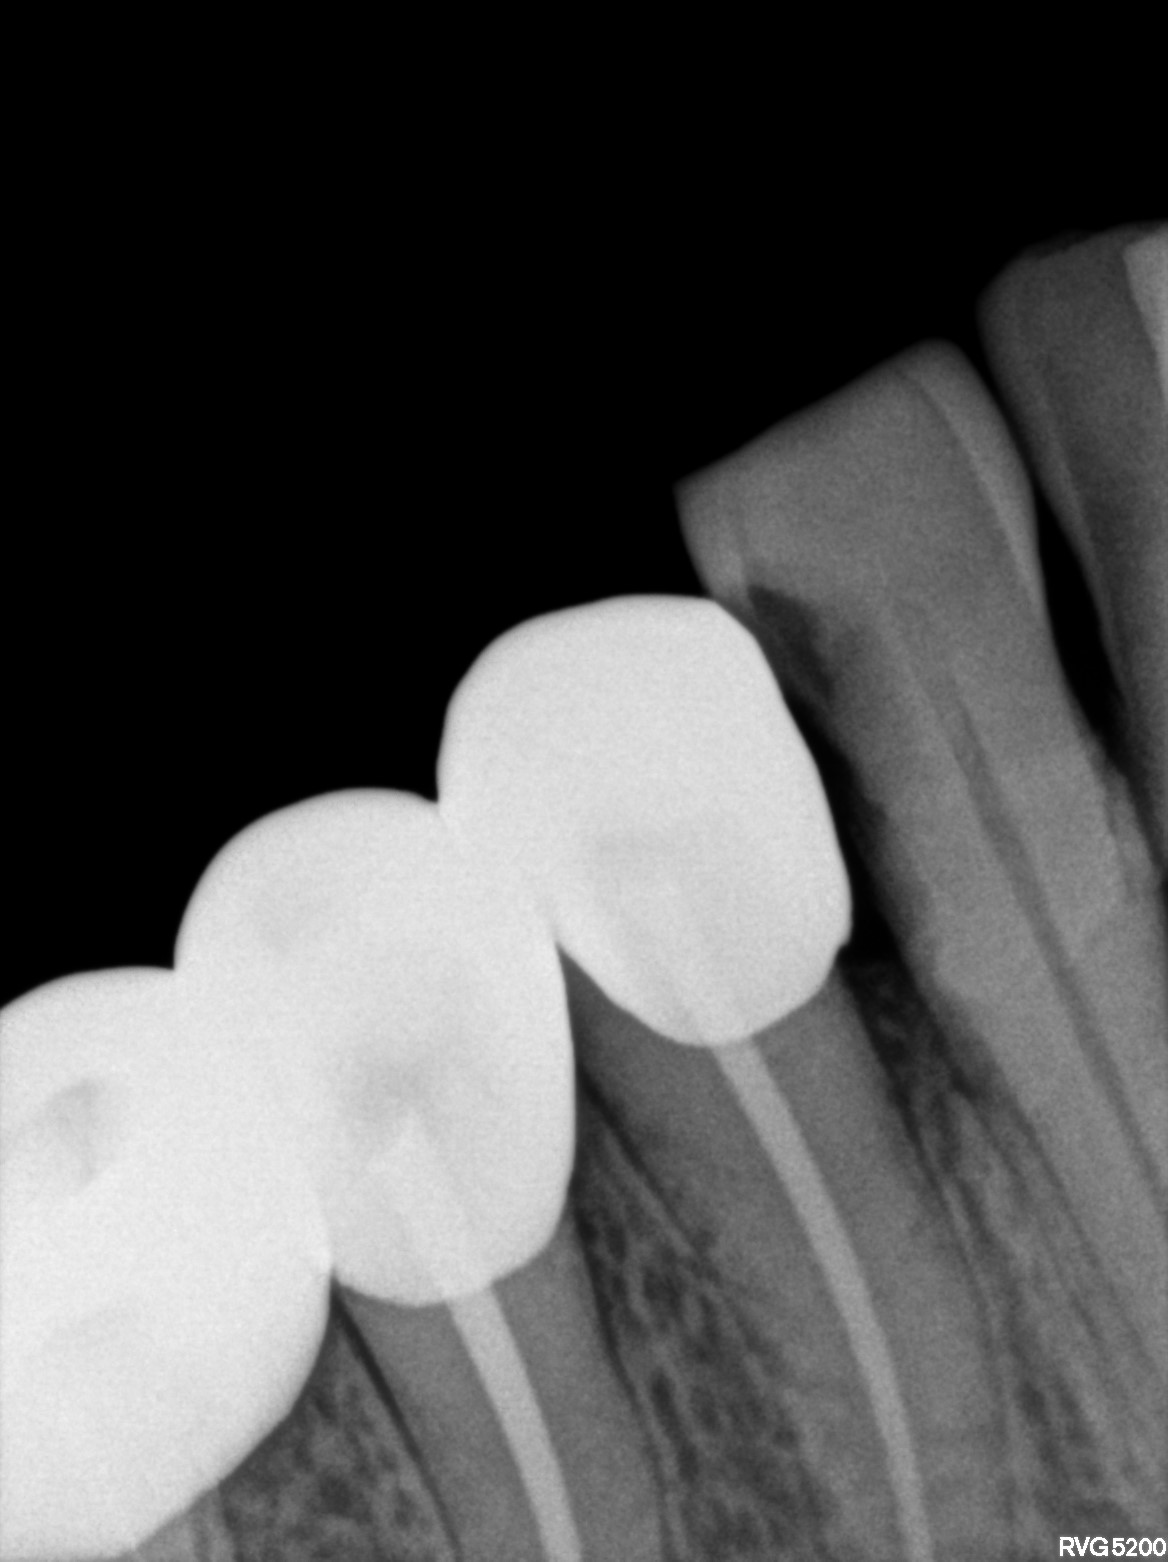

Dental Radiographs FHIR: DocumentReference · LOINC 24641-7

d (1).jpg

24641-7

xray_1772525715_0.jpg